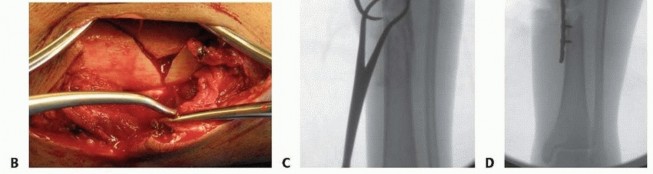

### TECH FIG 6 • Reduction of a simple middle diaphyseal fracture. A. AP radiograph of an oblique spiral distal tibia fracture. B. Use fluoroscopy to demonstrate fracture lines and localize clamp incision locations and clamp positions. C. Pointed reduction clamps can be placed through small stab incisions. D,E. AP and lateral fluoroscopic image demonstrating fracture reduction with percutaneous clamp application. Fracture Reduction ### Simple Middle Diaphyseal Fractures (Transverse or Short Oblique) Manual traction with gross manipulation will reduce simple transverse mid-diaphyseal fractures. Medially based external fixation or distraction with a large universal distractor is helpful for reduction when no assistants are available, in large patients, or when used for provisional fixation. Muscular paralysis is often helpful. Placement of percutaneous pointed reduction forceps can be helpful in oblique and short oblique patterns to achieve anatomic or near-anatomic reduction. Use fluoroscopy to mark the level and orientation of the fracture on the skin to facilitate the reduction clamp orientation and ideal placement of skin incisions. Introduce a small or large pointed clamp under and through skin stab wounds; care must be taken to maintain clamp points against bone ( TECH FIG 6A-C). Typically, the spike on the distal fragment is posterolateral. ### Highly Comminuted Middle Diaphyseal Fractures Have comparison radiographic images of the uninjured extremity available to be used as a template for length and rotational reduction landmarks. 556 Mechanical traction with medially based half-pin fixation is very helpful. A large external fixator or large universal distractor is equally effective. The proximal Schanz is placed posteriorly and parallel to the tibial plateau ( TECH FIG 7A). The distal Schanz pin is placed just above and parallel to the plafond ( TECH FIG 7B). The intramedullary reduction tool available in most nail or reamer sets can be used to manipulate the proximal fragment in order to advance the tool across the fracture, which achieves fracture reduction and guidewire placement. ### Open Middle Diaphyseal Fractures Large segmental and butterfly fragments that are completely devitalized and void of soft tissue attachments should be removed and cleaned of contamination. These pieces can be reintroduced into the fracture site and used to perform anatomic open reduction following passage of the intramedullary rod and interlocking. These pieces should be removed after fixation is completed because they represent a large amount of nonviable material in a high-risk wound.

### TECH FIG 7 • A. AP radiograph of a comminuted segmental tibial fracture. B-D. Intraoperative AP and lateral fluoroscopic imaging of the knee and lateral view of the ankle showing appropriate application of the large universal distractor with resultant reduction. A posteriorly positioned half-pin is helpful for fracture reduction and does not block nail passage. E. Clinical image showing application of large universal distractor. F-H. Postoperative AP and lateral radiographs of the knee and tibia showing successful fixation. Occasionally, an osteotome is required to free near-circumferential fragments ( TECH FIG 8A-C). If reduction is difficult, a small fragment unicortical plate can be used to maintain the reduction during reaming and nail placement. Once interlocking is completed, the plate should be removed ( TECH FIG 8D). Passing the Guidewire Once optimal AP and lateral plane reduction is achieved, the wire is advanced past the level of the fracture. Verify that the wire is within the canal on both the AP and lateral views to avoid advancing too far and damaging extramedullary structures. In metadiaphyseal fractures, the wire must be centered in the metaphyseal segment. In proximal and distal fractures, blocking screws or half-pins may be required to ensure centralized positioning of the guidewire ( TECH FIG 9A). 557